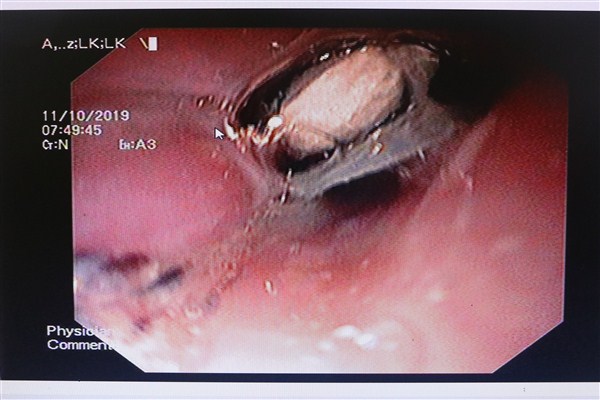

Ngay khi tiếp nhận, bác sĩ khám bệnh nghi ngờ bệnh nhân có dị vật đường thực quản nên chỉ định Nội soi thực quản - dạ dày gắp kiểm tra. Khi tiến hành nội soi, các bác sĩ phát hiện đoạn thực quản cổ có dị vật nằm ở 1/3 đoạn thực quản phía dưới của bệnh nhân. Kíp nội soi đã tiến hành gắp dị vật là một viên thuốc lẫn vỏ (thuốc chưa tách ra khỏi vỉ) kích thước 2x2cm.

Nội soi thấy vỉ thuốc nằm ở 1/3 đoạn thực quản phía dưới của bệnh nhân